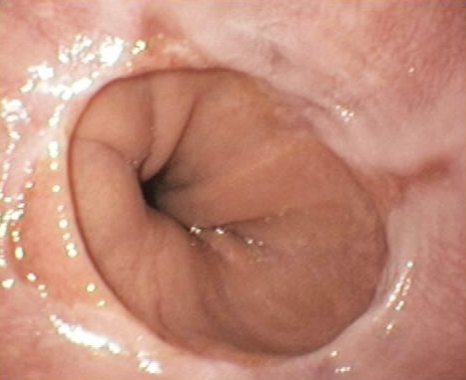

É fundamental realizar uma endoscópica digestiva alta para confirmar o diagnóstico.

Para estabelecer o diagnóstico e medir a intensidade do refluxo, podem ser necessários exames adicionais como: radiografia, pHmetria e manometria do esôfago.

Endoscopia mostrando hérnia de hiato com esofagite de refluxo intensa